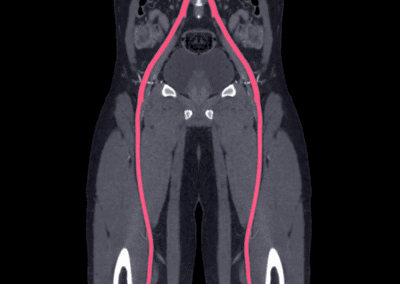

L’arteriopatia napoli è una condizione che coinvolge il restringimento o il blocco delle arterie, che può compromettere il flusso sanguigno e causare gravi complicazioni.

Il Dr. Demetrio Guarnaccia, chirurgo vascolare esperto, offre trattamenti avanzati per l’arteriopatia napoli, mirando a ripristinare una corretta circolazione e prevenire le complicazioni.

- Angioplastica: Un intervento minimamente invasivo per dilatare le arterie ristrette, ripristinando il flusso sanguigno.

- Bypass arterioso: Nei casi più gravi, un intervento chirurgico per creare una nuova via per il flusso sanguigno, bypassando le arterie ostruite.